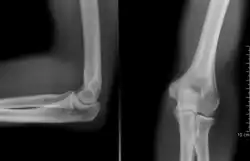

Codo humano izquierdo extendido

Codo humano izquierdo flexionado